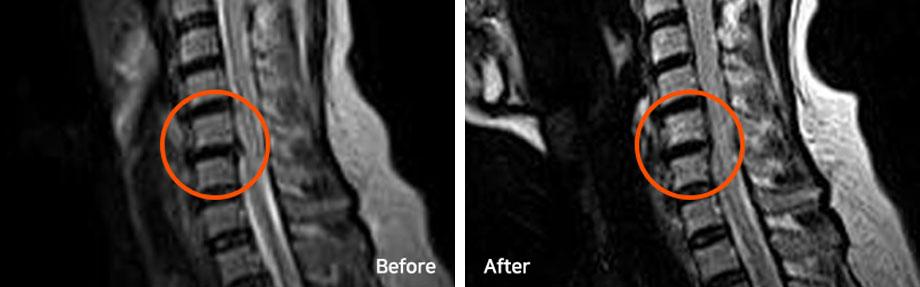

※ After 사진은 6개월 후 촬영된 모습으로, 파열된 디스크가 깨끗하게 흡수된 것을 확인할 수 있습니다. (치료기간-입원치료 4주, 외래치료 1개월 / ABCDE 복합 치료법)

파열된 목디스크는 치료를 잘 받으면서 충분한 휴식을 취하면 우리 몸으로 흡수되어 없어지는 경우가 많고, 파열이 심할수록 오히려 더 잘 흡수되기도 합니다.

단, 디스크로 다시 재흡수되는 것이 아니라 우리 몸의 대식세포 등이 튀어나온 디스크를 이물질로 인식해 녹여서 몸속으로 흡수되어 없어지는 것입니다.